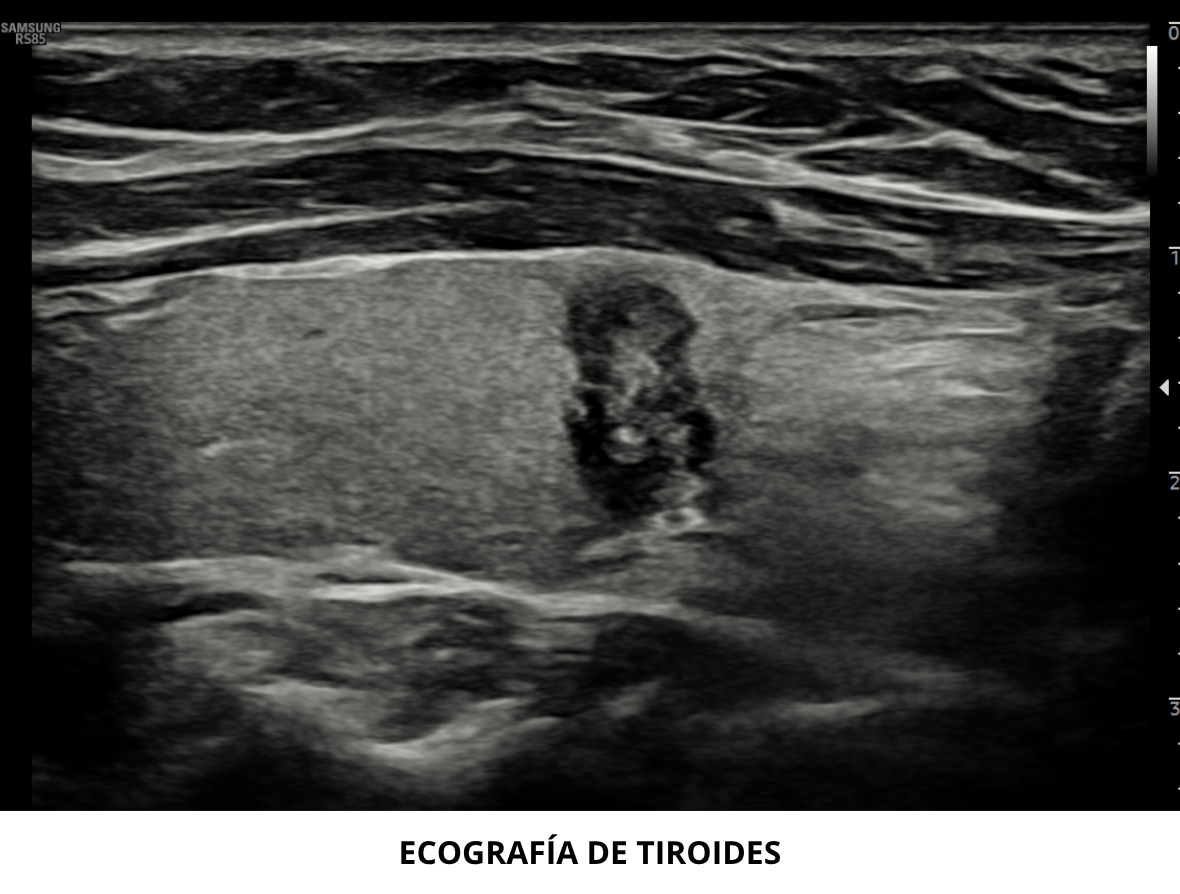

Ecografía de Tiroides

La ecografía de tiroides en la actualidad es el examen de el...